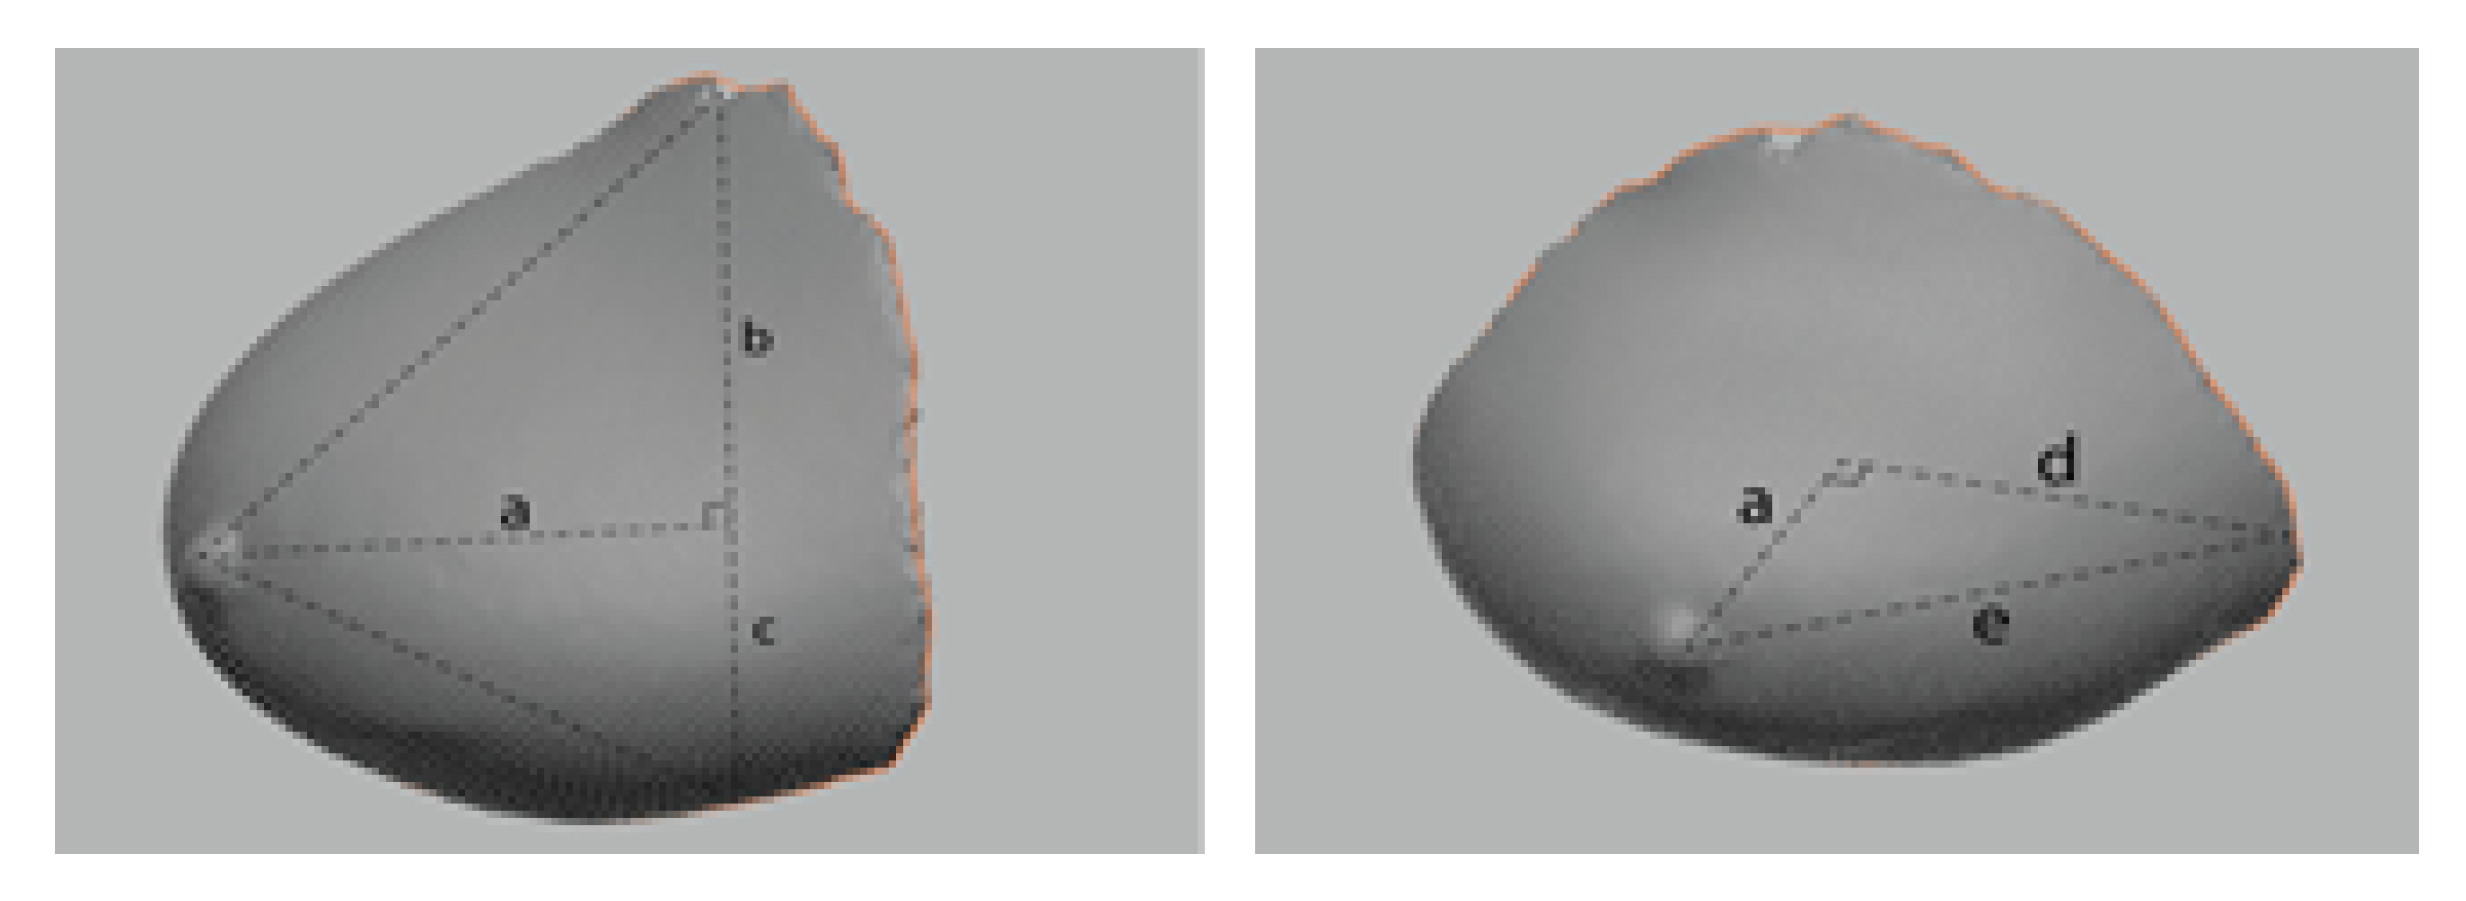

3.5. Comparison of Breast Volume Data Based on Human Body Data Images

As MRI requires the patient to lie prone on the device and let the breasts droop through the holes of the bed, the image obtained is in a long ellipsoid shape (sloth), whereas 3D-SIM is scanned in a standing position, and thus, the bust rises above the rib cage. Lee et al. [47] conducted extensive research on breasts and assumed them to be in various shapes, such as a cone, arc, and semicircle. Assuming that saggy breasts are cone-shaped, the correlation coefficient was r2 = 0.607, which was suggested as the most suitable method. Eder et al. [48] claimed that breasts are a complex of various shapes, and thus it is efficient to measure the volume by dividing them rather than applying one cubic form. Thus, this study adopted a method to obtain the volume by dividing breasts by bust point as shown in study [48] rather than measuring a single form, like Lee et al. [47]. As the participants in this study had saggy breasts, this study used the method of obtaining cone volume, which is suitable for saggy breasts, as suggested by Lee et al. [47] (Figure 6). Therefore, using this method, the volume of the breasts in 3D-SIM data was obtained with the assumption that the upper part is in the cone shape and the lower part is in the ellipsoid shape on the sagittal plane. All of the participants’ breasts were divided based on the bust point and were separated into upper and lower parts of breasts by connecting the surface line between the medial and lateral bust points around the bust point. The length of the superior and interior bust points was divided into three even parts on average by the connecting surface line between the medial and lateral bust points around the bust point, showing a cone shape up to the point of 2/3, while the bottom part showed the shape of 1/4 ellipsoid, on the sagittal plane. Therefore, to measure the volume of 3D-SIM, the cone volume formula was applied to the upper part of the breast, while the ellipsoid volume formula was applied to the lower part (Formula (1)). This is the 3D-SIM volume calculation formula.

Figure 6.

The 3D-SIM volume calculation.